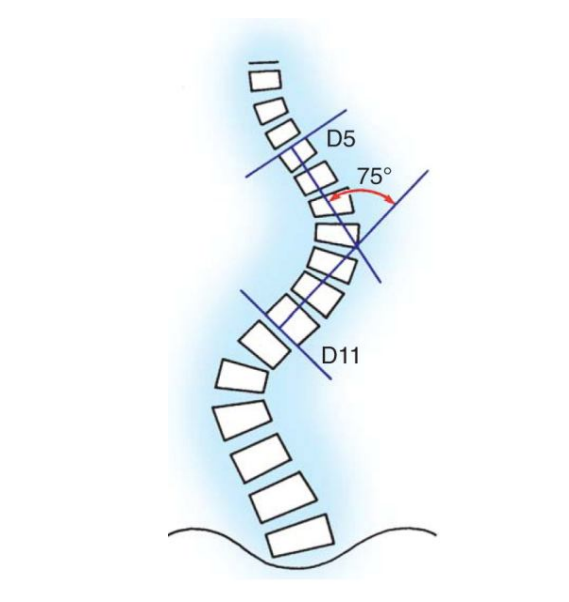

Khoa Phẫu thuật thần kinh cột sống Vẹo cột sống (VCS) vô căn là biến dạng cột sống phổ biến nhất ở trẻ nhỏ và thanh thiếu niên, nó chiếm khoảng 80% tất cả các trường hợp VCS. Những biến dạng của cột sống và lồng ngực trong VCS vô căn ảnh hưởng đến vẻ […]